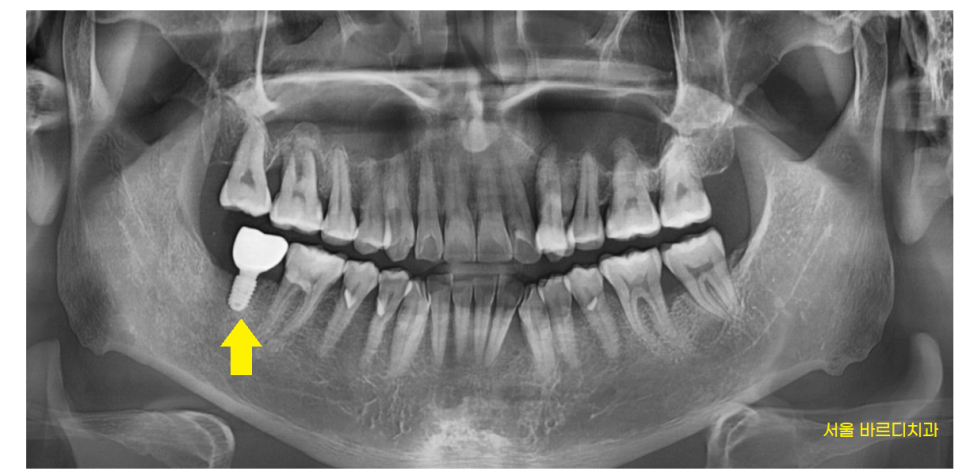

240518

발치 후 3개월정도 기다렸습니다.

기다린 이유는

환자분의 자연 치유 능력을 기다렸습니다.

뼈이식을 하더라도

내 뼈가 얼마나 남아있느냐에 따라

임플란트 예후는 달라지니까요~

잇몸뼈가 어느정도 차고 나서

임플란트 수술을 진행하였습니다.

240622

잇몸 욱신 욱신 원인이

뼈가 녹은거라

임플란트와 내 뼈가 충분히 결합될 수 있도록

기다려주었습니다.

안정적인 상황에서

머리를 만들어드리는 과정을 진행해드렸고

240720

문제의 치아 해결해드렸기에

이제 씹을 때마다 통증

안녕~~

▼덕풍동 임플란트 결과▼